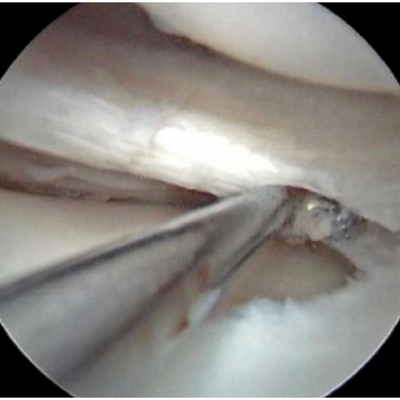

Click on an image below to view more info.